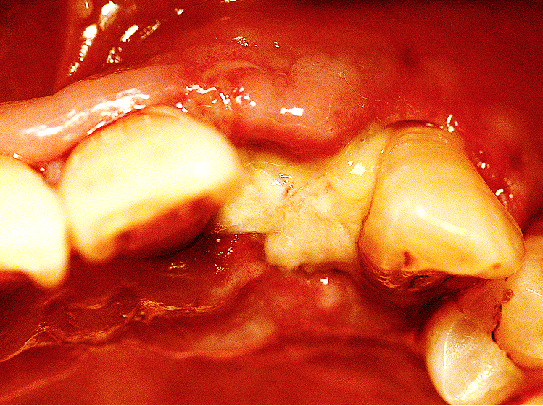

使用12#镰形刀片沿21、22、23做龈沟内切口,于24近中做垂直附加切口。

翻开全厚粘骨膜瓣,暴露22颊侧牙槽骨,微创拔除22。

搔刮22拔牙创,暴露22牙槽骨表面,开放骨髓腔。